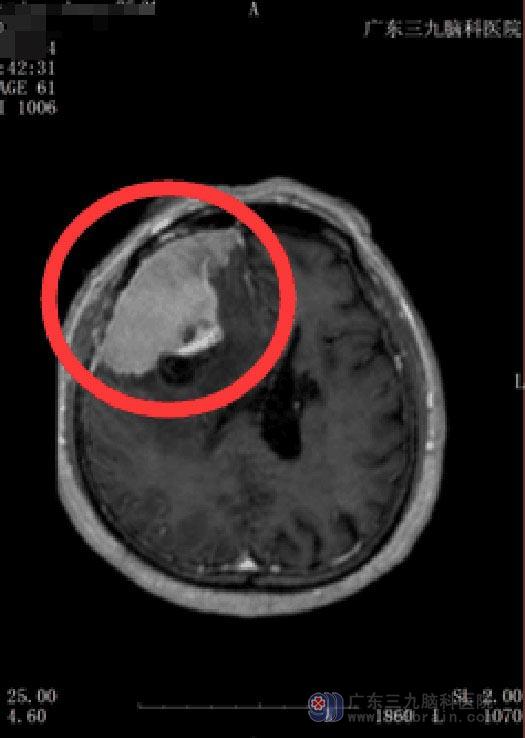

广东三九脑科医院颅脑MR提示:1.右侧额部占位性病变,范围约为7.6cm×3.8cm×4.9cm,考虑为脑膜瘤可能;2.右侧大脑镰下疝形成;3.左侧基底节-放射冠区陈旧性腔梗灶;4.右侧横窦及乙状窦显影偏细,考虑为发育因素;5.双侧筛窦、左侧上颌窦及蝶窦炎症。

大脑镰下疝多为一侧幕上占位性病变所引起,有时可因大脑前动脉受大脑镰压迫而发生同侧额叶内侧面或旁中央小叶的软化,出现对侧下肢瘫、感觉减退和排尿功能障碍等症状。